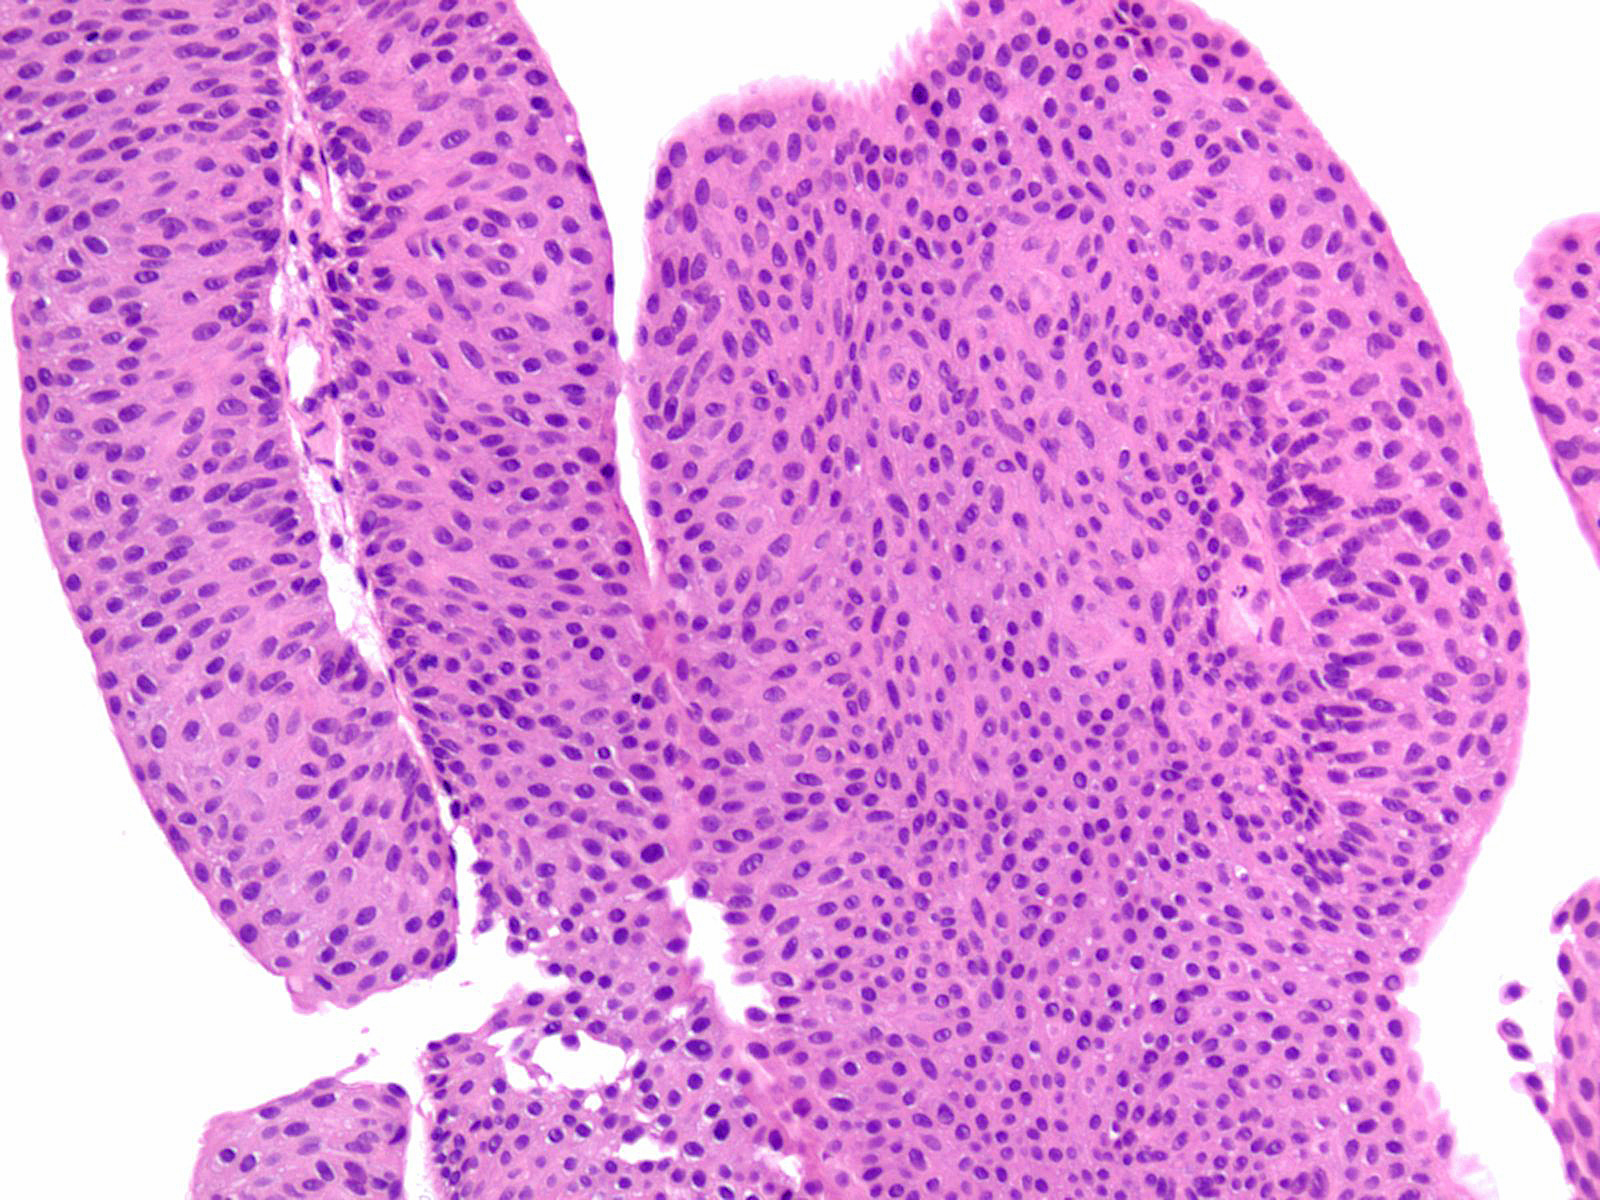

Consensus grade: Low-grade papillary urothelial carcinoma (LG-PUC)

Case description (by case creator):

Lesion shows moderate variation in nuclear size, shape and chromatin. Scattered nuclei are significantly enlarged and hyperchromatic relative to other nuclei. Lesion still maintains an overall orderly appearance.